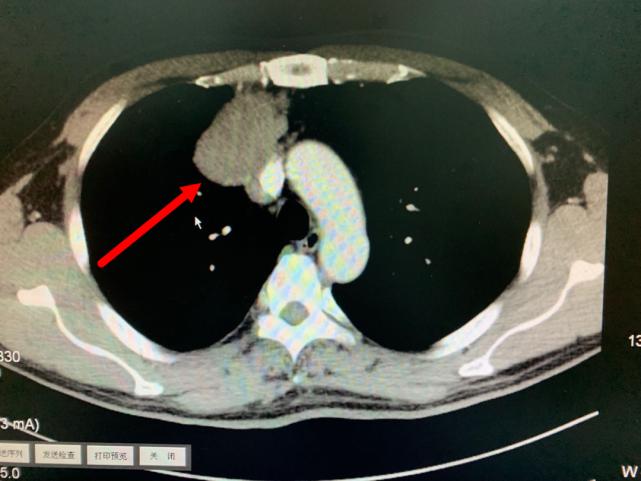

箭头所指为巨大纵隔肿瘤

肿瘤与周围血管存在黏连

今年11月份,老方因“肠炎”在浙江省立同德医院肛肠科住院。“新冠”期间住院需要常规做胸部CT筛查,检查出来的结果却让他和医生们大吃一惊,胸部CT显示:胸腔内存在一个巨大肿瘤即纵膈肿瘤,大小约10.0cm×6.5cm×7.0cm,大小和一个成人男性拳头差不多。肿瘤紧靠着肺部、心脏及大血管,且与部分大血管有粘连,对重要的脏器已经造成了挤压。在确定胃肠道没有严重病患后,老方被转入心胸外科进一步作检查、治疗。

叶中瑞主任医师通过进一步增强CT检查发现,老方体内的肿瘤巨大、与相邻的重要脏器粘连,界限不清,手术难度较大,且微创手术不适合,于是采取正中劈开胸骨的手术方式。手术过程顺利,术后恢复良好。第二天即下床活动。术后病理结果显示:纵膈肿瘤性质为中度恶性的胸腺肿瘤,后续还需要做进一步的放射治疗,以防止复发。老方在庆辛之余,他告诉叶中瑞主任医师,自己从今年开始每年都按时做体检,争取做到疾病早发现、早治疗,避免错过疾病的最佳治疗时机。